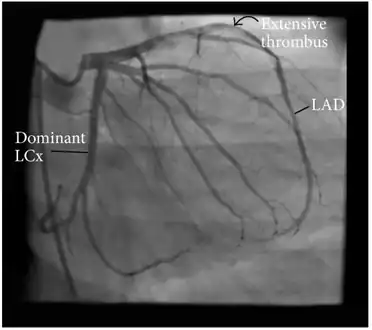

Angiographic image showing extensive LAD thrombosis -

Coronary angiography of an MI patient